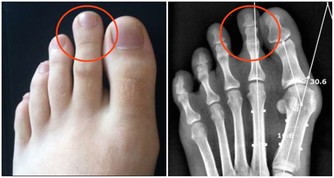

3、影響身高:

由於性激素的提前催發,骨骺閉合也將大大提前,生長期相應變短,影響身高。